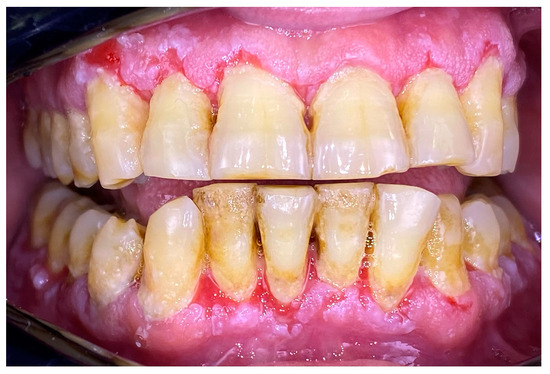

2.2. Clinical Case 2—Pemphigus Vulgaris (PV)